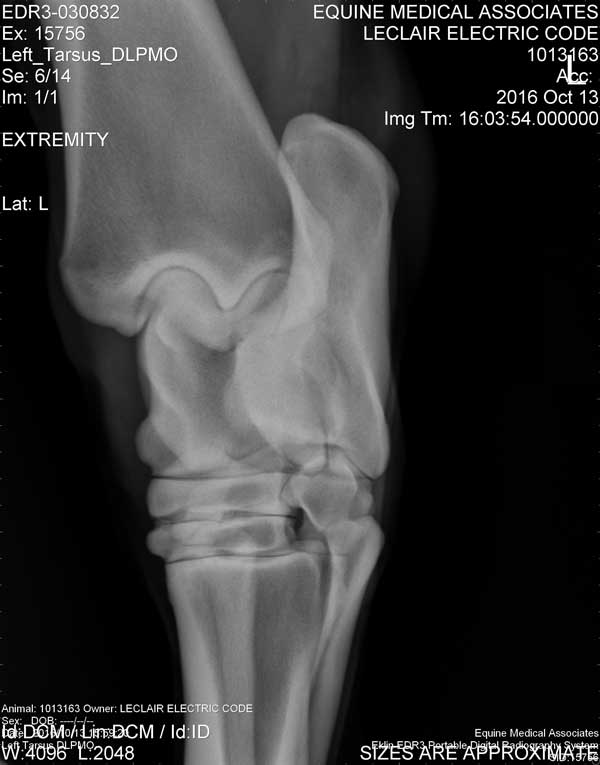

Electric Code is 11 years old at the time these X-Rays were taken on October 13, 2016

Hock/Tarsal

Left